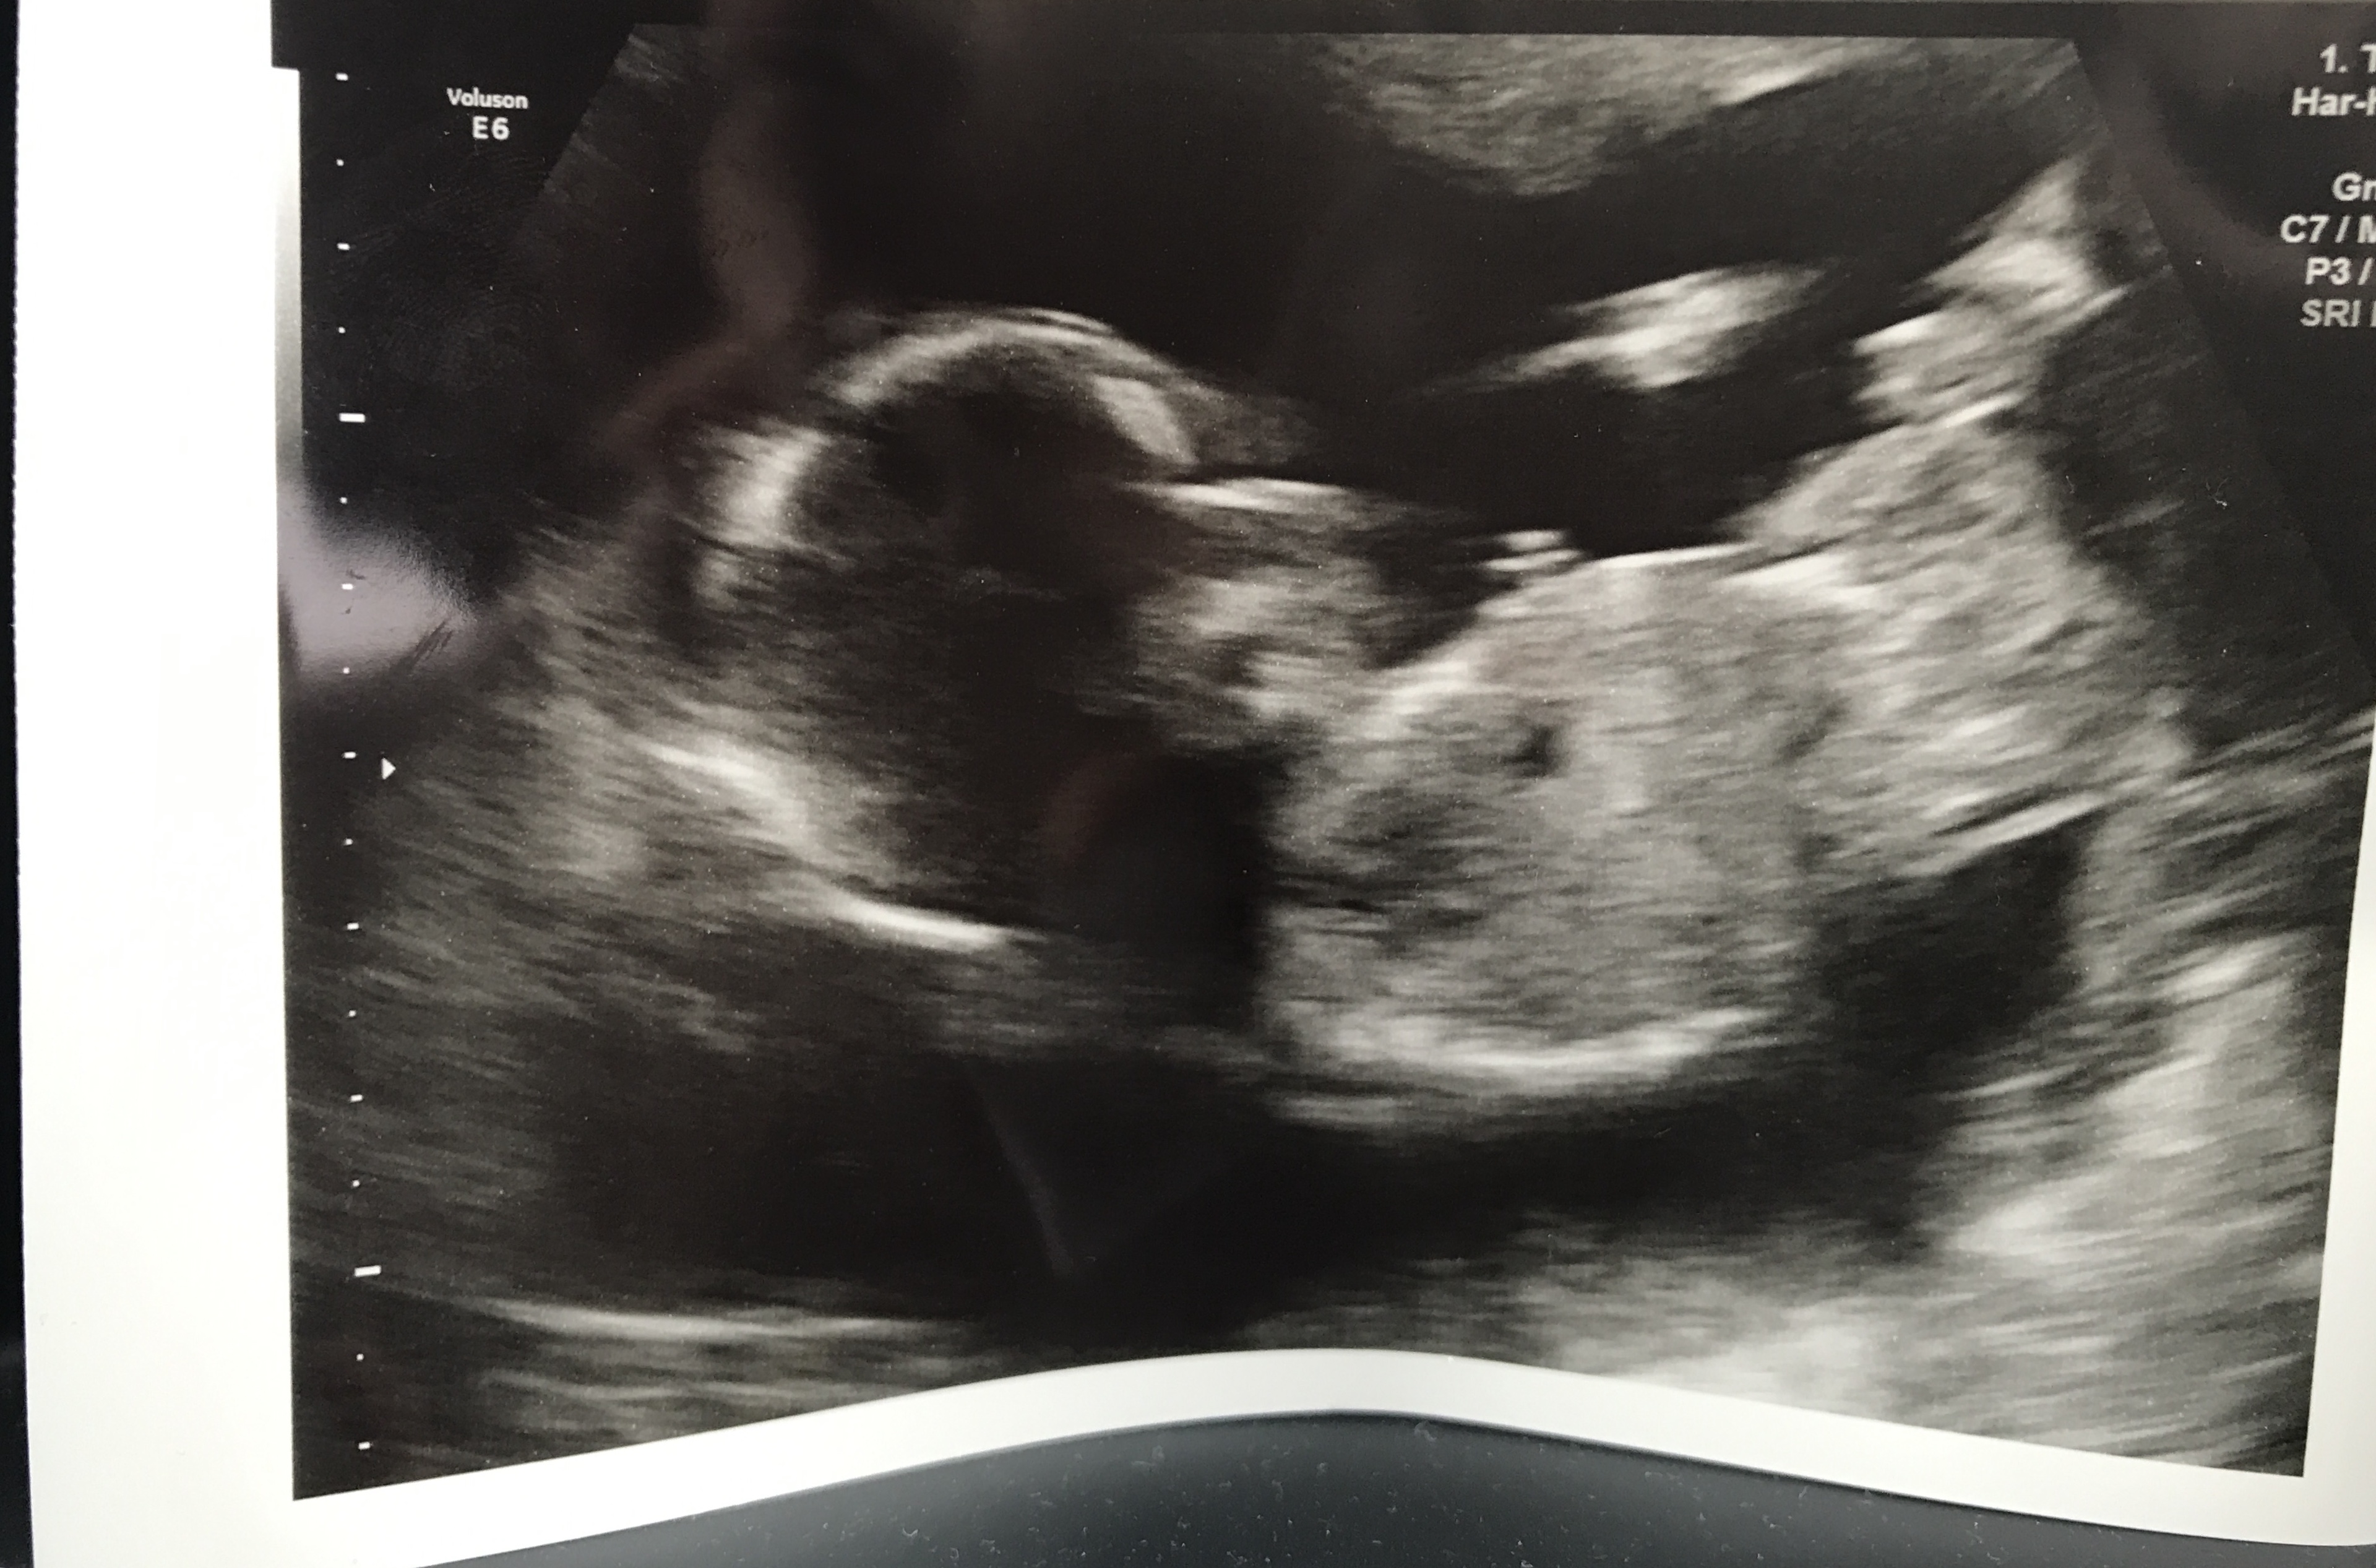

My stubborn little bean wouldn’t uncross their legs so we are none the wiser after our gender scan! Does the skull theory still apply at 16 weeks? I’m so desperate to know and won’t find out now til after Christmas! Attachment 40943